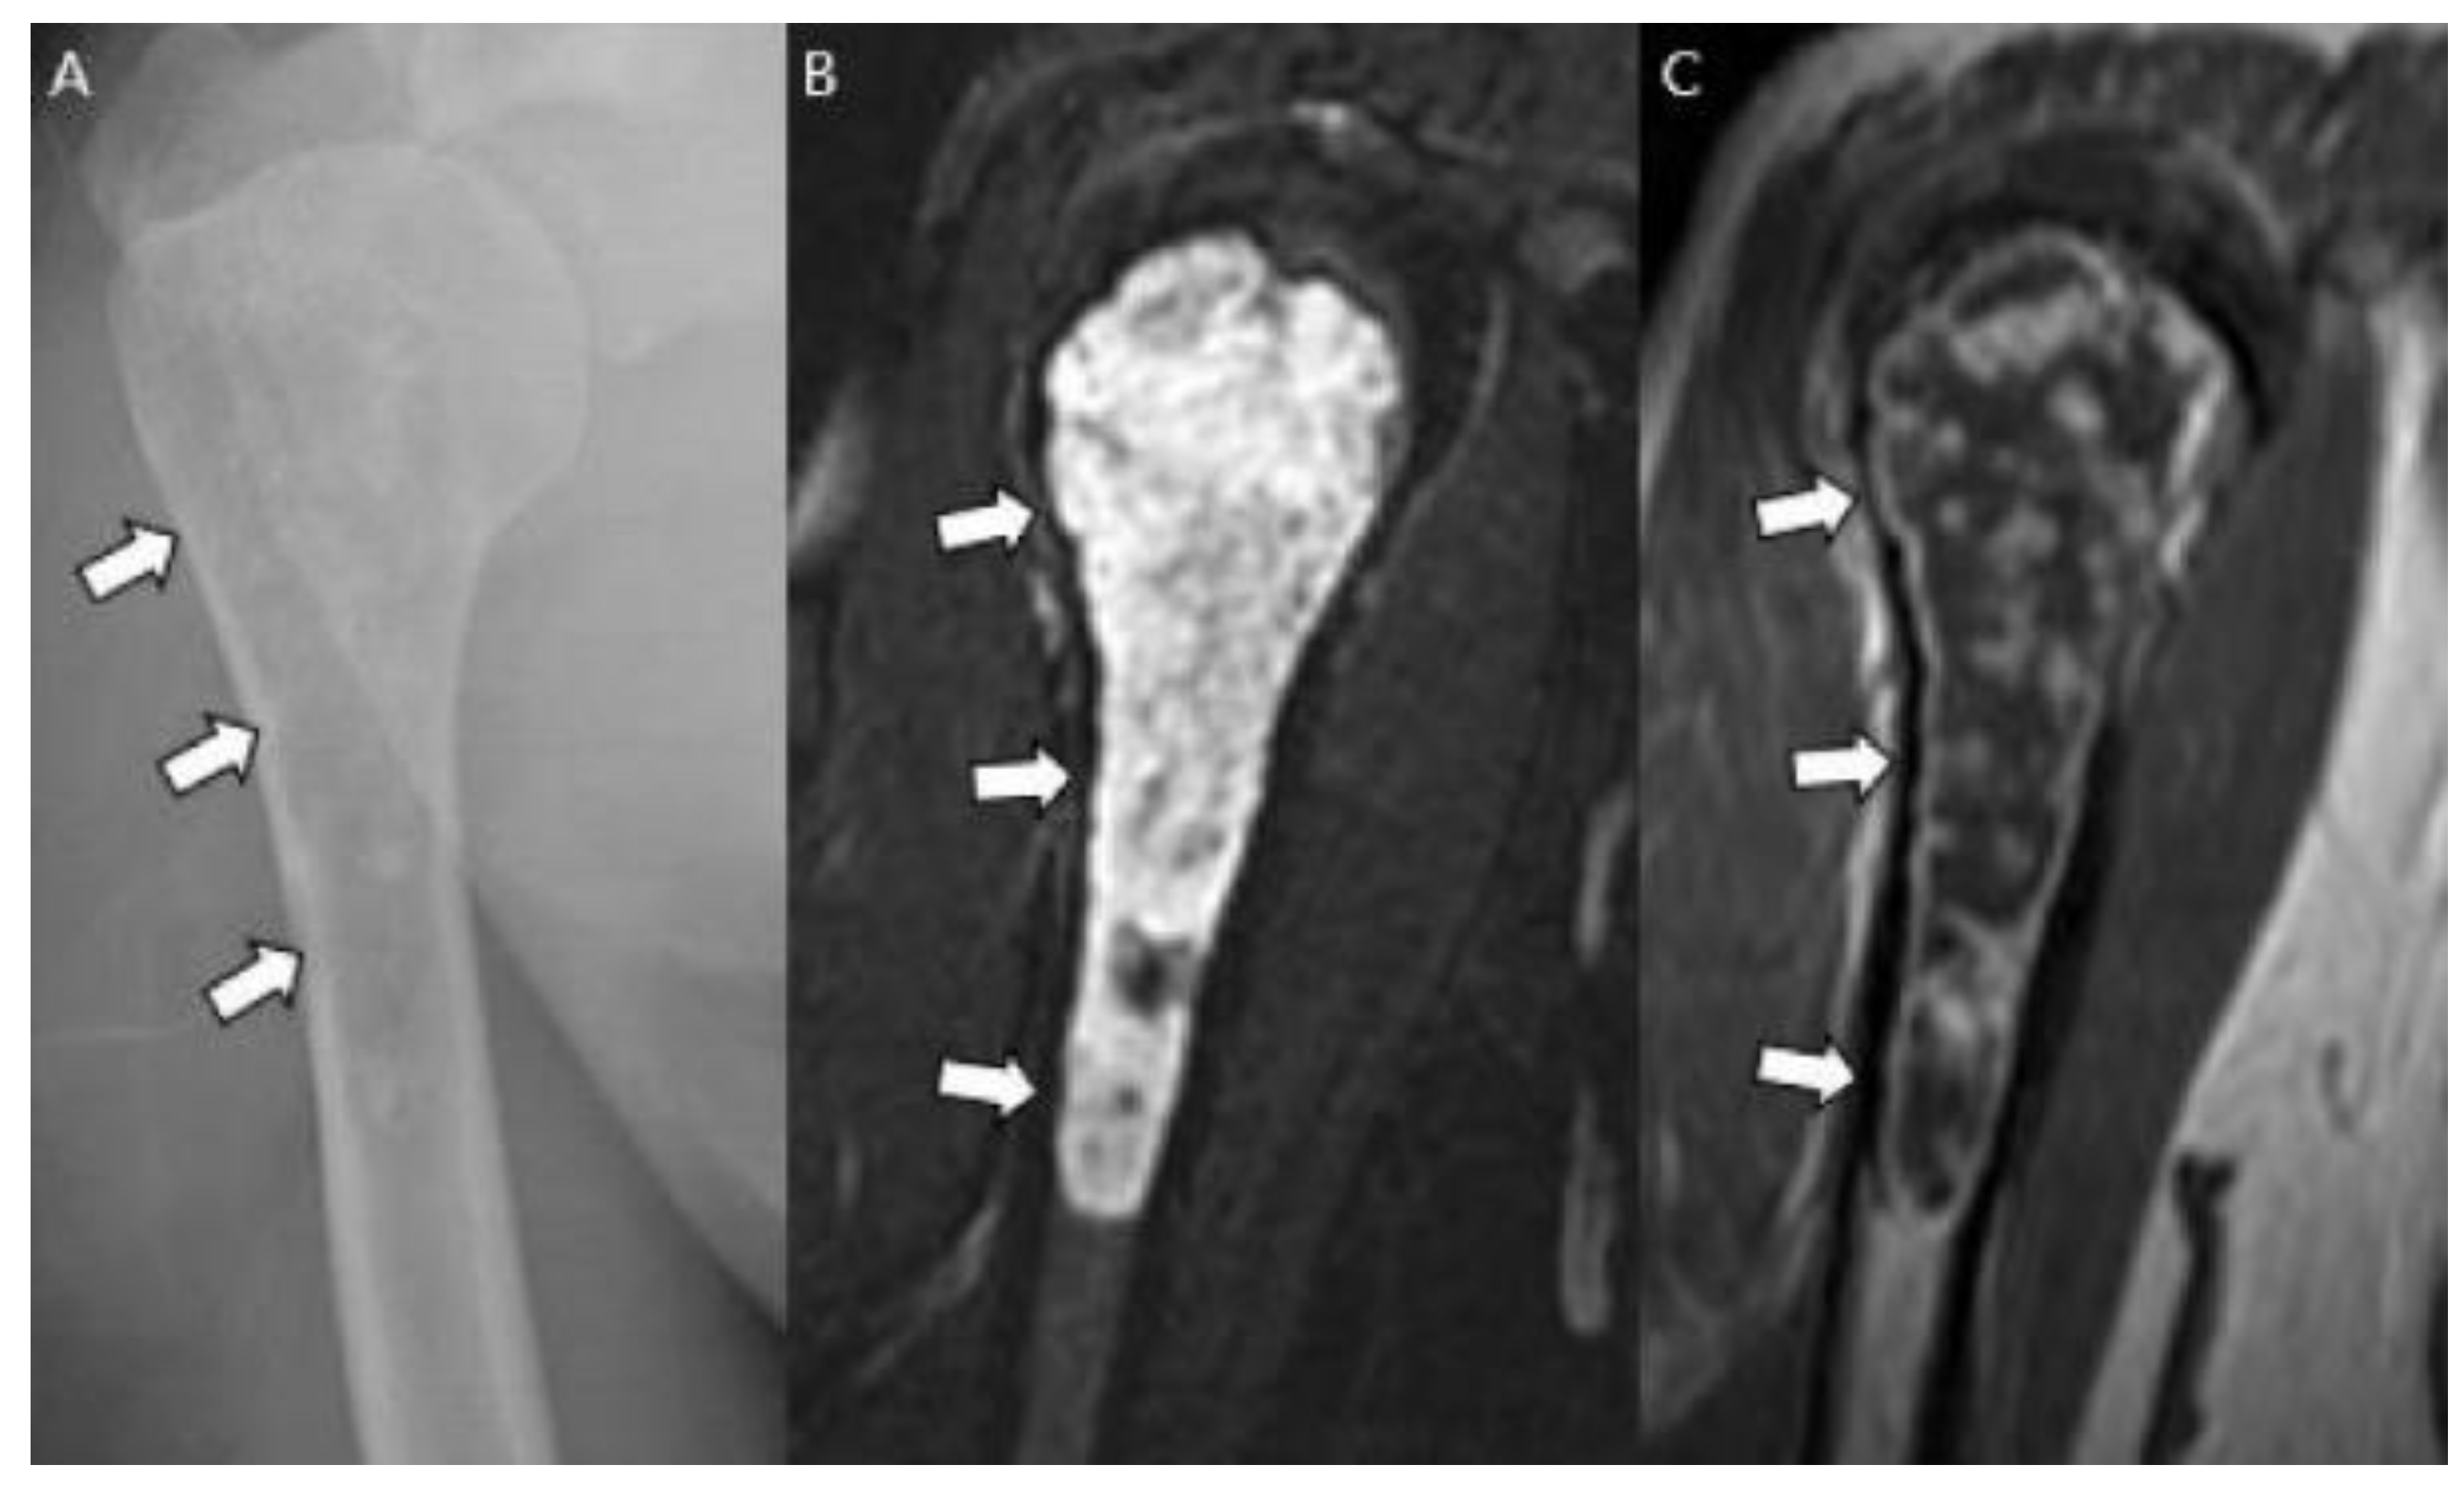

- Jain, V.; Oliveira, I.; Chavda, A.; Khoo, M.; Saifuddin, A. MRI differentiation of low-grade and high-grade chondrosarcoma of the shoulder girdle, chest wall and pelvis: A pictorial review based on 111 consecutive cases. Br. J. Radiol. 2021, 94, 20201404. [Google Scholar] [CrossRef] [PubMed]

- Douis, H.; Singh, L.; Saifuddin, A. MRI differentiation of low-grade from high-grade appendicular chondrosarcoma. Eur. Radiol. 2013, 24, 232–240. [Google Scholar] [CrossRef] [PubMed]

- Yoo, H.J.; Hong, S.H.; Choi, J.-Y.; Moon, K.C.; Kim, H.-S.; Kang, H.S. Differentiating high-grade from low-grade chondrosarcoma with MR imaging. Eur. Radiol. 2009, 19, 3008–3014. [Google Scholar] [CrossRef]